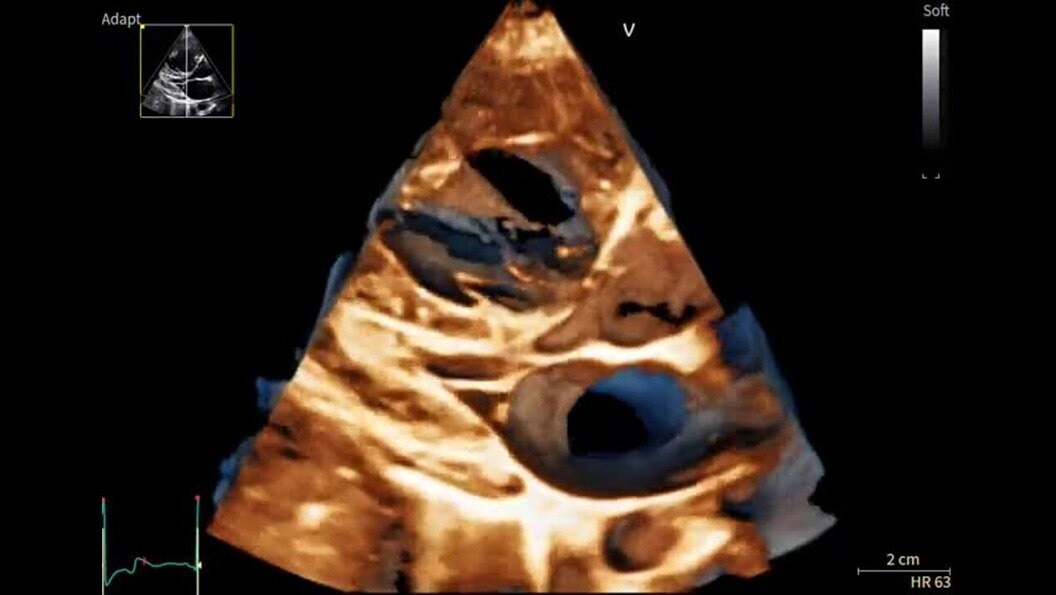

Designed to take you further, next-generation cSound Pioneer works in harmony with our sophisticated probe technology to deliver enhanced detail, a new level of Color Flow, and incredible 4D imaging for clinical confidence from the first scan.

With outstanding image quality that sharpens borders, boosts clarity, and enhances definition between structures, Vivid Pioneer forms the foundation for AI-driven insights you can trust. Simplify and streamline measurements and quantification with automated tools, and rely on artificial intelligence that supports consistent, reliable results across users.